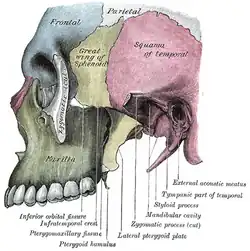

Visão lateral do crânio. Fossa infratemporal esquerda.

Fossa infratemporal esquerda. O crânio da frente.